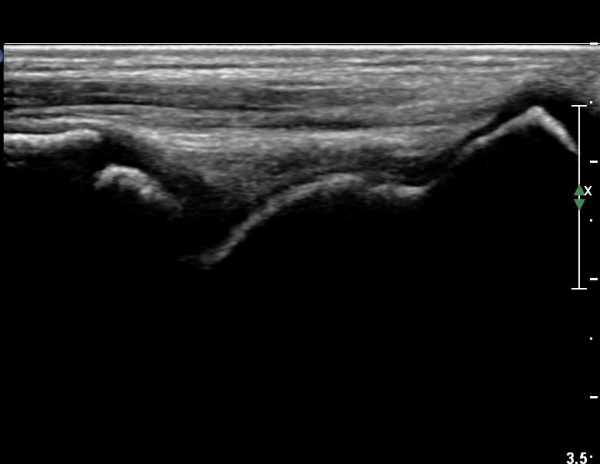

ÃÊÀ½ÆÄ °Ë»ç